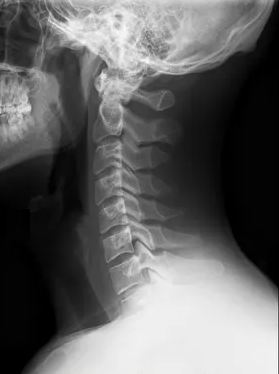

O sistema auditivo integra aferências somatossensoriais do trigêmeo e das raízes cervicais superiores já no núcleo coclear dorsal. Clinicamente, movimentos cervicais, mandibulares, posturais, respiratórios ou oculares podem modular o zumbido. Esse fenômeno, frequentemente tratado como subtipo etiológico, pode ter maior relevância prognóstica.